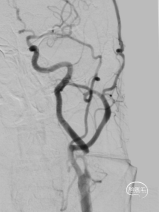

术前DSA。

右侧正侧位造影。

DSA可见:左侧颈内动脉C1段重度狭窄,狭窄率约90%。